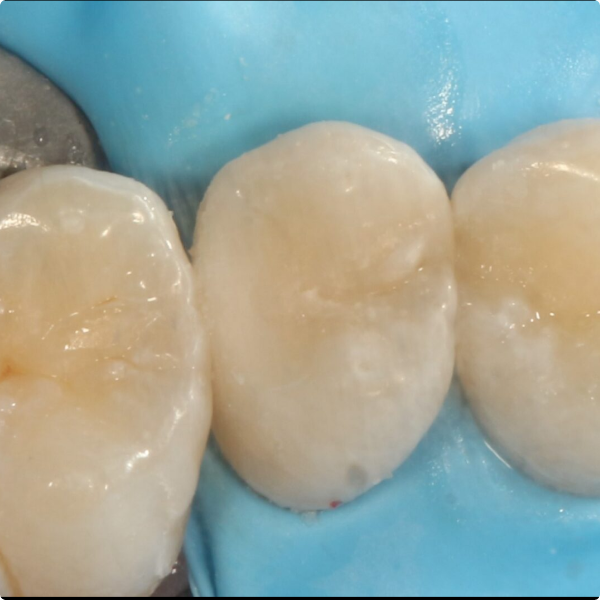

Although Stela can be used without a rubber-dam, Dr Shankla opted for one to maintain optimal isolation and control. After removing the decayed tissue, photographs were taken to document the cavity’s extent. A sectional matrix was placed to ensure proper contact, given the size of the lesion, then the Stela system was applied.

Stela simplifies the restoration process via a two-step protocol: first the primer (just 15 seconds), then the composite. The composite’s user-friendly consistency allowed sculpting before the material set, reducing procedural time and complexity.

The restoration was straightforward and efficient, taking less time than a traditional amalgam or multi-stage composite workflow. By using Stela, Dr Shankla reduced instrument use and the number of procedural steps making the treatment more cost- and time-effective. After placement, she allowed a few minutes for self-curing, then completed final trimming and polishing all without the need of a curing light.